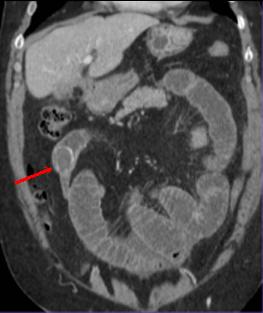

| L'occlusion par bride et

adherence represente de 50% des occlusions

intestinales . Aspect TDM particuliairement est

image de bec des oiseaux ( fleche rouge ) au niveau

de l'obtacle . Image de distension de l'intestin sus

- lesionelle et image hydro-aerique transitionnel .

L'intestin sous -lesionelle est collabe totale |

Image TDM en coupe

sagitale : Occlusion de l'intestin aigue avec

signe de bec de oiseaux ( fleche rouge ) et

dilatation intestinale en amont et signe de feces (

retention de feces au niveau de l'intestin sus -lesionelle |